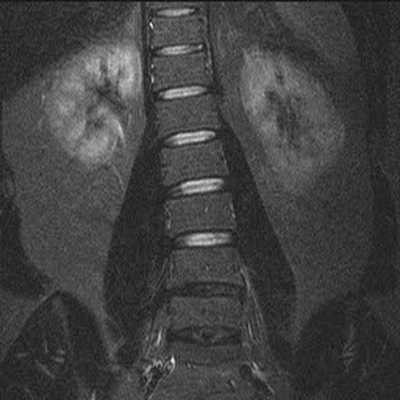

Гемангиомы на снимке МРТ поясничного отдела позвоночника в коронарной проекции

Гемангиомы на снимке МРТ пояснично-крестцового отдела, Т2 взвешенное изображение